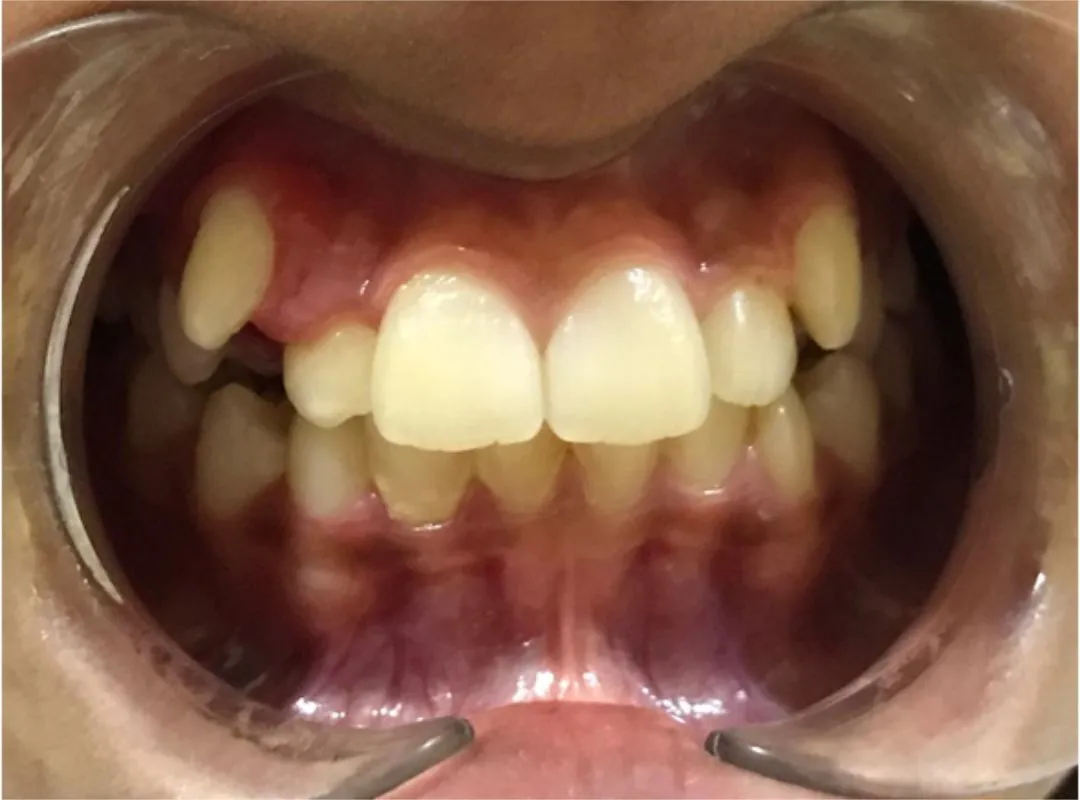

I especially appreciate their expertise in interceptive orthodontics which made a significant difference in my child’s dental development

I had undergone my teeth Aligner process at JP dental, Perambur,which was over a period of 8 months. Journey was of 12 levels of aligners and after each level my teeth were thoroughly evaluated to ensure the process was smooth and progressive. The doctors here are very professional and have upto date equipments which gave me a very great outcome from my journey here. Highly recommend .create a caption for this review